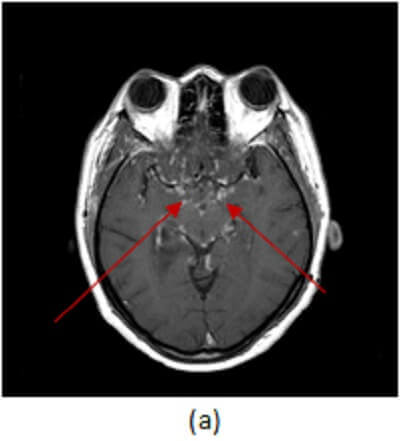

Figure 1: (a, red arrow) axial postcontrast T1 demonstrates enhancement of the leptomeningeal surface along the basal cisterns. (b, blue arrow) Sagittal T2 of the spine demonstrates increased T2 signal involving an expanded cervical cord. (c, green arrow) Sagittal T1 post contrast of the spine and brain demonstrates intramedullary and leptomeningeal enhancement of the cervical cord, along with parasellar, frontal and cerebellar leptomeningeal enhancement.

Leptomeningeal (pial and arachnoid) involvement with perimedullary enhancement is most common, with preferential involvement of the parasellar region and the cranial nerves, especially the optic chiasm. Predilection for these spaces can help distinguish sarcoid from other causes of leptomeningeal enhancement like meningitis, metastatic disease, vasculitis and subacute infarct. Enhancing intraparenchymal granulomas may also be seen in neurosarcoid. Complications include hydrocephalus and vasculitis.

Diagnosis: Neurosarcoid